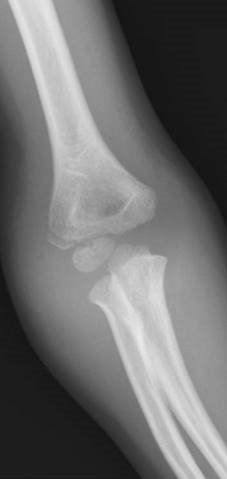

Describe the injury to me. Can you classify it?

This is AP radiograph showing a displaced lateral condyle fracture.

Traditionally this injury is classifi ed using the Milch system. This depends on whether the fracture exits into the joint relative to the trochlea. It has not been shown to be that useful in terms of guiding management. More important is whether the fracture extends into the joint.

How would you estimate this childโs age from the radiograph?

I would estimate the age based on the fact that the ossifi cation centres around the childโs elbow appear in a standard order:

z Capitellum, 1 year z Radial head, 3 years z Medial epicondyle, 5 years z Trochlea, 7 years z Olecranon, 9 years z Lateral epicondyle, 11 years

This is an isolated closed injuryโhow would you manage this defi nitively?

M y defi nitive management of this injury would consist of open reduction of the displaced fragment and internal fi xation to achieve absolute stability. I would hold my reduction with a partially threaded, small-fragment 3.5-mm screw. I would approach the fracture from the lateral side and check my reduction anteriorly avoiding the neurovascular posterior structures. Post-operatively I would protect the soft tissues in a backslab for 3 weeks, and then once they had healed I would start early range of motion exercises.

What are some of the complications of this particular injury?

T hese fractures have an unusually high rate of non-union for a childrenโs fracture so interfragmentary compression with a lag screw is the optimum treatment. Other complications include angular deformity (cubitis valgus) secondary to a lateral growth arrest (more so in Milch Type 1 fractures). Management of such a deformity remains controversial. In my institution we would only consider an osteotomy at a later date if the deformity gave the child a functional problem. Tardy ulna nerve palsy is also a late, and luckily rare, complication.